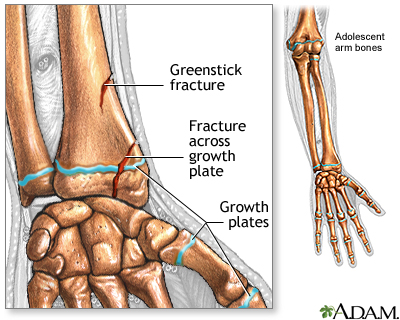

If more pressure is put on a bone than it can stand, it will split or break. A break of any size is called a fracture. If the broken bone punctures the skin, it is called an open fracture (compound fracture).

If a young child refuses to put weight on an arm or leg after an accident, won't move the arm or leg, or you can clearly see a deformity, assume the child has a broken bone and get medical help.